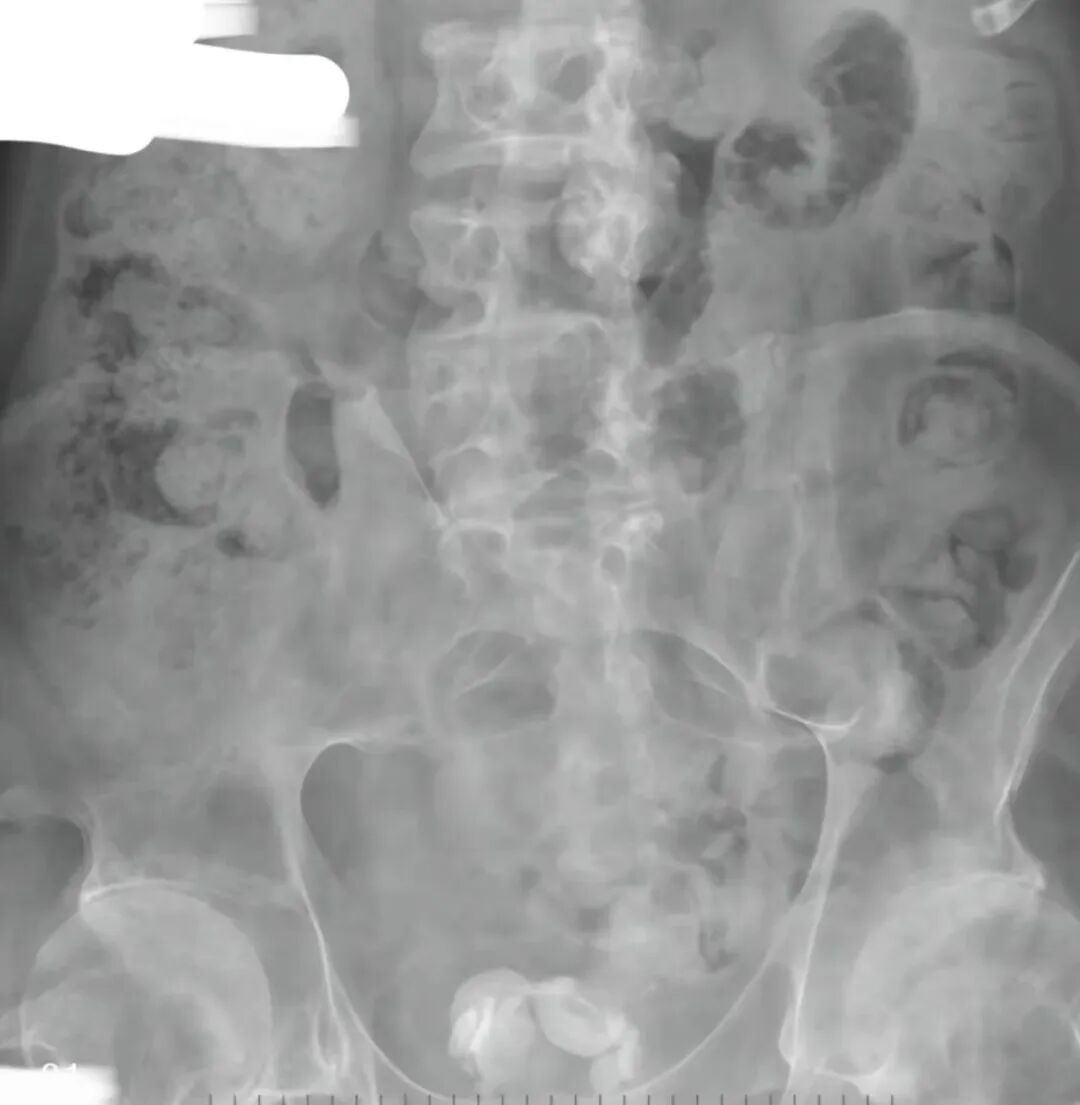

(左图为术前   右图为术后腹部平片)

术中,患者膀胱腔内填满结石,大小不一,大者约3.0cm,小的约1.0cm,整个膀胱腔内全是结石。

从内镜下看密密麻麻结石,泌尿外科团队45分钟的“与石搏斗”手术在镜下未见结石残留、膀胱粘膜无明显出血,持续膀胱冲洗液清亮后宣布结束。